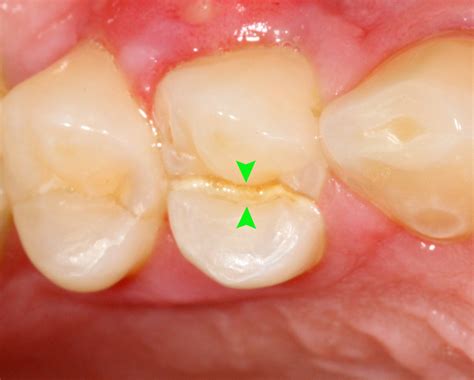

Not all cracks are created equal. Dentists categorize them based on severity and location. Understanding these classifications can help you grasp the urgency of your specific situation.

Classification Characteristics

Craze Lines Surface-level cracks in the enamel; usually cosmetic and harmless.

Fractured Cusp A piece of the chewing surface breaks off; usually limited to the crown.

Cracked Tooth A crack extending from the chewing surface toward the root.

Split Tooth A severe crack that separates the tooth into distinct segments.

Vertical Root Fracture A crack starting at the root and moving upward toward the crown.